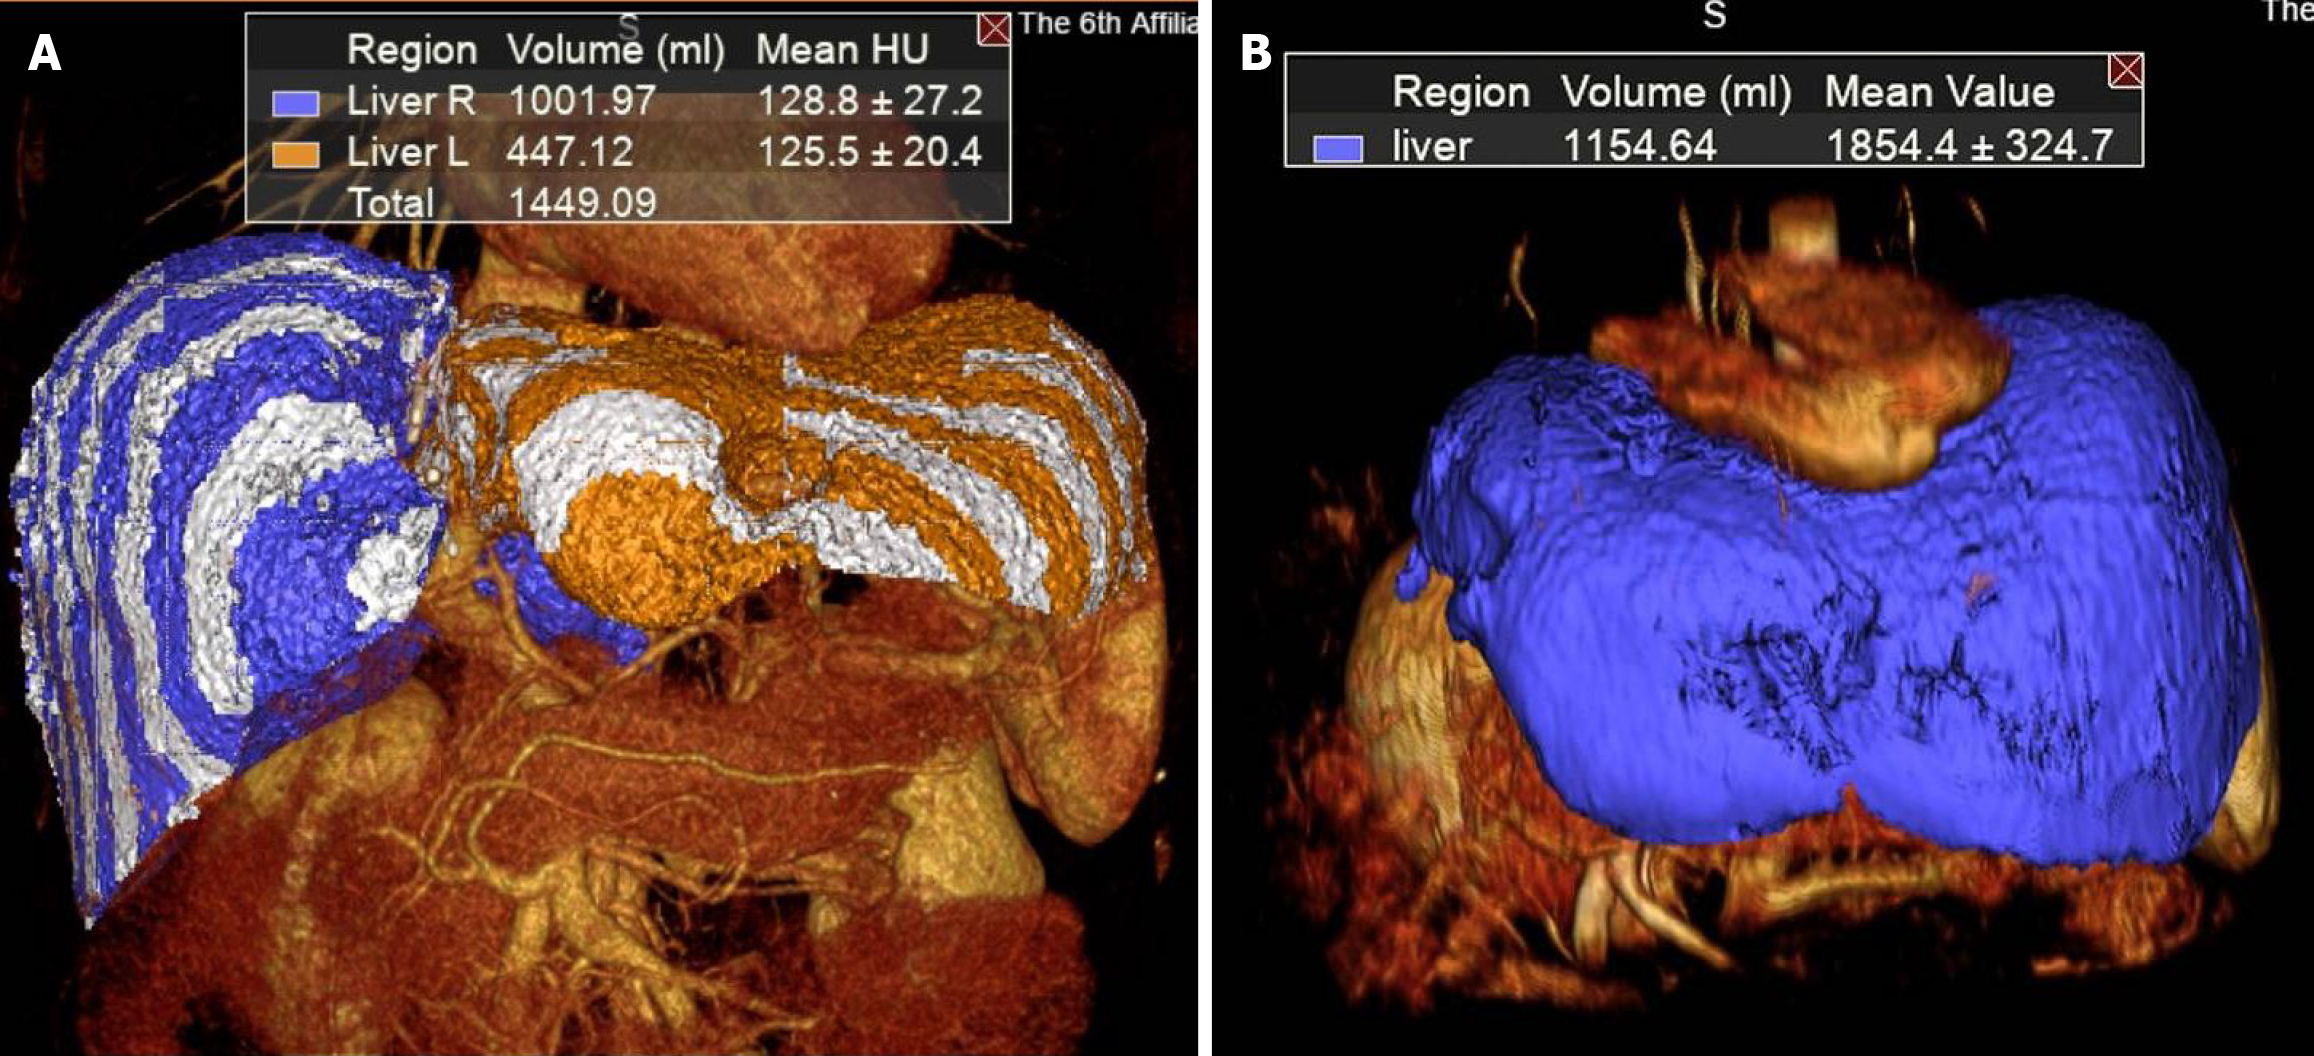

Figure 4 Regeneration of future liver remnant in the period of post-associating liver partition and portal vein ligation for staged hepatectomy.

A: Future liver remnant volume before stage 2 (447.1 mL); B: Future liver remnant volume at 3 months after stage 2 (1154.6 mL).